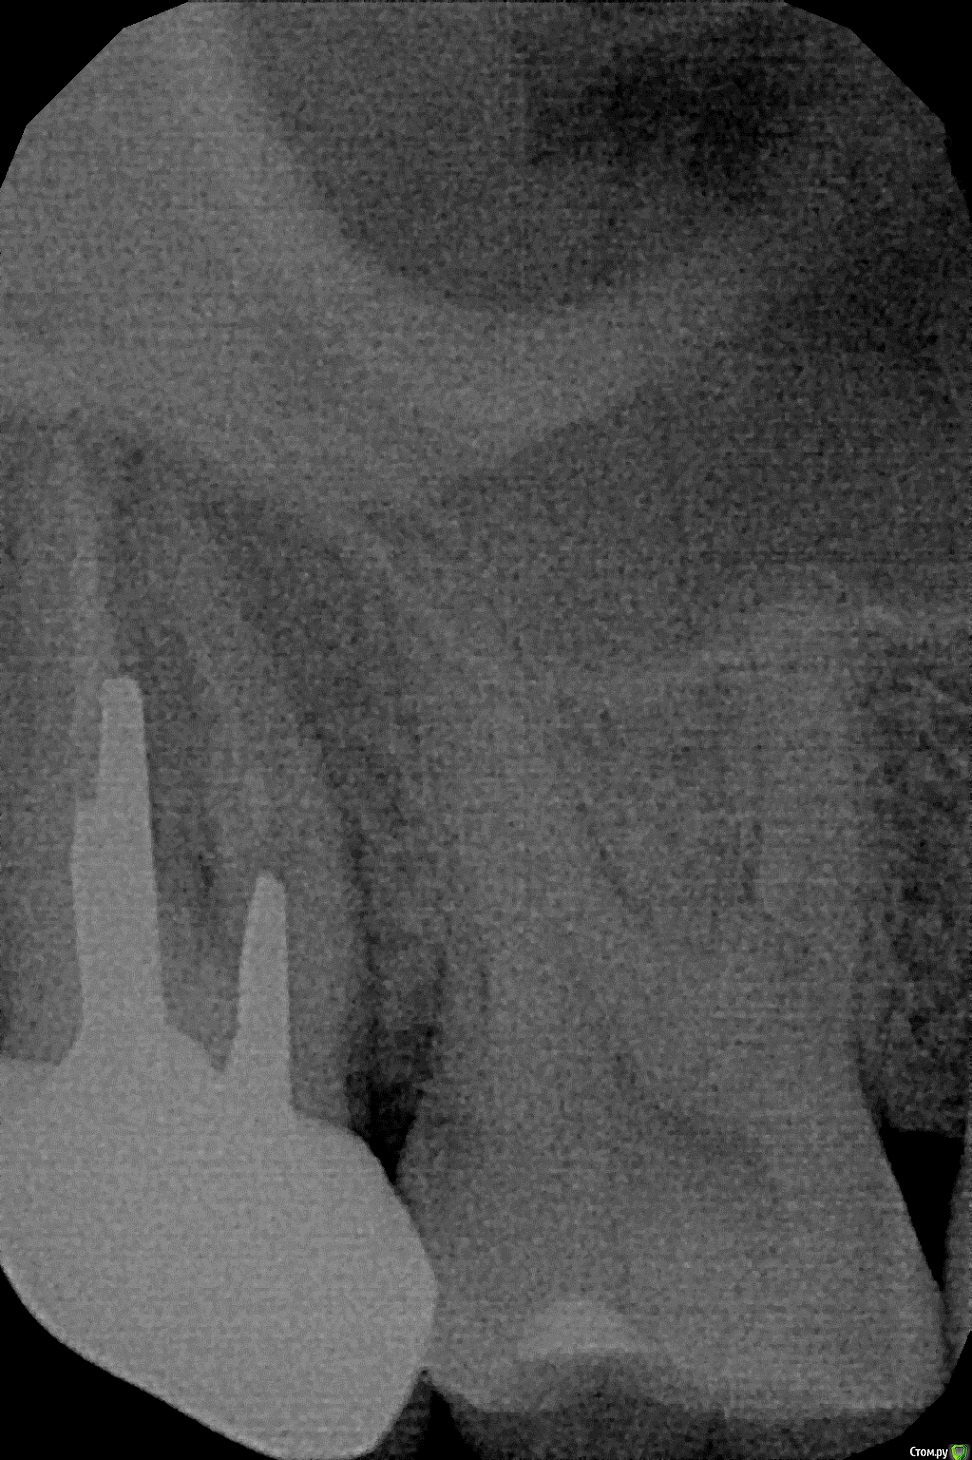

viavvv Опубликовано 25 февраля, 2017 Поделиться Опубликовано 25 февраля, 2017 Добрый день! Хотелось бы узнать мнение врачей по ситуации.Верхние восьмёрки давно удалены.Каналы в верхней 7-ке были запломбированы более 5 лет назад, и тогда же была установлена культевая вкладка + коронка. 5 лет зуб не беспокоил никак.Недавно в командировке зуб 7ка заболел.Боль проявлялась при нажатии на зуб, а также была лёгкая постоянная боль, которая утихала после полоскания тёплой солёной водой. Через 6 дней вернулся в Москву, показался стоматологу, он сделал рентген и по нему сказал:1) есть воспаление у корня2) лечить зуб не удастся, т.к. такую культевую вкладку достать нельзя - она стоит враспорку3) каналы запломбированы не до конца4) сказал, что может "дать лекарство", но зуб будет болеть и в будущем - при любом ослаблении иммунитета5) поэтому нужно удалять Зуб удалили. Врач сказал, что через полгода можно приходить, ставить имплант. Спустя несколько дней после удаления зуба изучил тему и похожие случаи на форумах, выяснил про то, что вкладку в некоторых случаях можно убрать ультразвуком и начал сомневаться в решении доктора - а можно ли было всё-таки убрать вкладку и вылечить зуб, обойдясь без удаления? Рентген прикладываю. Спасибо Ссылка на комментарий

viavvv Опубликовано 1 марта, 2017 Автор Поделиться Опубликовано 1 марта, 2017 Спасибо.А по рентгену - можете, пожалуйста, подсказать - как выглядит и где именно тут воспаление?На аналогичных снимках в интернете увидел, что воспаление отображается чёрной областью на рентгене, а тут я не вижу этой области.. Ссылка на комментарий